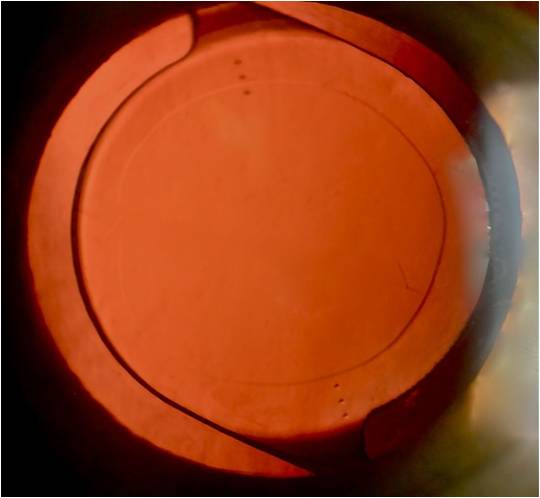

Cuando el deterioro visual producido por la catarata entorpece las actividades de la persona; debe ser operado. La cirugía de catarata actual o facoemulsicación ultrasónica permite, a través de micro incisiones introducir finas sondas que aspiran el cristalino cataratoso y en su lugar implantan un lente que permita enfocar.

Tras una rápida recuperación posquirúrgica se recetarán lentes ópticos para neutralizar defectos residuales. Si la retina y el nervio óptico se encuentran en buen estado: la visión obtenida satisfacera plenamente las necesidades del operado.